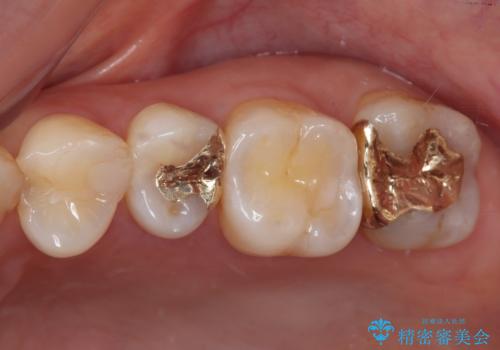

ゴールドは「白い歯」ではありませんが、銀歯の金属色とは異なり、非常にきれいな色合いが特徴です。

もちろん、適合が極めて良いという圧倒的メリットもゴールドクラウンやゴールドインレーの特徴です。

- 奥歯の銀歯をすべてゴールドにすることを希望された患者様です。

セラミックインレーによる補綴治療も提案しましたが、ご自身で強い咬合力を認識しており、歯にもインレーにもダメージの少ないゴールドインレーにて処置することとしました。